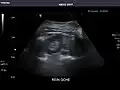

Left kidney -